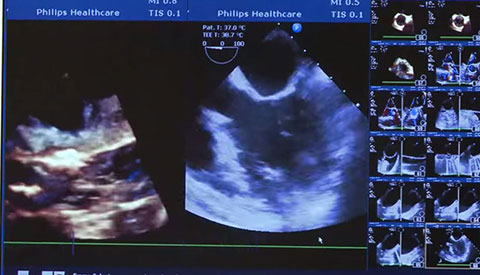

تم تشخيص أحد المرضى لديك بتضيّق في الصمام الأورطي المصحوب بأعراض. يبلغ عمر المريضة 85 عامًا وهي تعاني من السكري وارتفاع ضغط الدم. أنت تدرك خطورة وضعها الصحي ما يجعلها غير مناسبة لجراحة القلب ولكن يسمح لها بأن تكون مرشحة لاستبدال الصمام الأورطي باستخدام القسطرة (TAVR). في يومنا هذا، تمنح حلول التصوير المبتكرة والأجهزة التي تعمل عن طريق الجلد الأمل لبعض المرضى الذين لا تتوفر لهم حتى الآن أي خيارات علاجية أخرى.